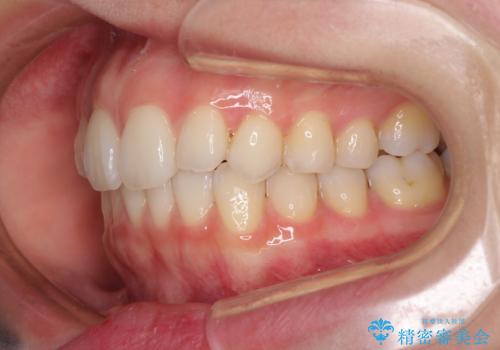

- 前歯のクロスバイトや残存している乳歯を気にして来院された患者様です。

上顎骨の幅が下顎骨よりも小さいので、拡大装置により骨幅を広げて上下関係を改善し、その後インビザラインにて歯並びを整えることとしました。

上下の骨幅を改善したことで、スムーズに歯列矯正を行うことができました。